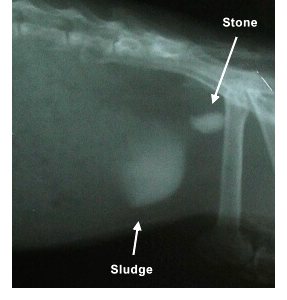

Močové kameny

Morčata jsou náchylná na tvorbu močových kamenů. Mohou být kdekoliv v močovém traktu, zpravidla se skládají ze soli vápníku: Fosforečnan vápenatý, Šťavelan vápenatý (Oxalát vápenatý). Často však z Uhličitan vápenatý, uvádí se až 90%

(Composition and Characteristics of Urinary Calculi from Guinea Pigs by Hawkins, et el, JAVMA Vol 234, No, 2, January 15, 2009).

Morčata přijímají ve stravě velké množství vápníku, který ve velkém množství zapříčiní vznik kamenů. Zároveň je důležitý poměr vápníku a fosforu ve stravě - ten by měl být 1,5:1 až 2:1 [vápník ku fosforu]

Diagnostika:

Veterinář ji provádí nejčastěji pomocí rentgenu , někdy lze kameny i nahmatat. Dalším vyšetřením je odběr a rozbor moči.

Léčba:

Lze léčit konzervativně nebo chirurgicky, v závislosti na druhu, typu kamene, velikosti a umístění. Velmi malé kaménky mohou být pečlivě sledovány pomocí testovacích proužků na přítomnost krve v moči, pravidelné rentgenové snímky a dietní úpravy. Chirurgické odstranění je léčba volena u velkých nebo bolestivých kamenů - nebo když hrozí ucpání močové trubice.

Je vhodné nasadit i antibiotika, která pomohou předcházet infekci (Bacrim, Biseptol)

Analgetika a další podpůrná léčba, jako jsou: brusinky, bylinný čaj, RodiCare URO, mohou být pro zotavení nezbytná.

Morčata musí být pravidelně kontrolována vzhledem k vysoké míře recidivy.

Močový kámen Rentgen